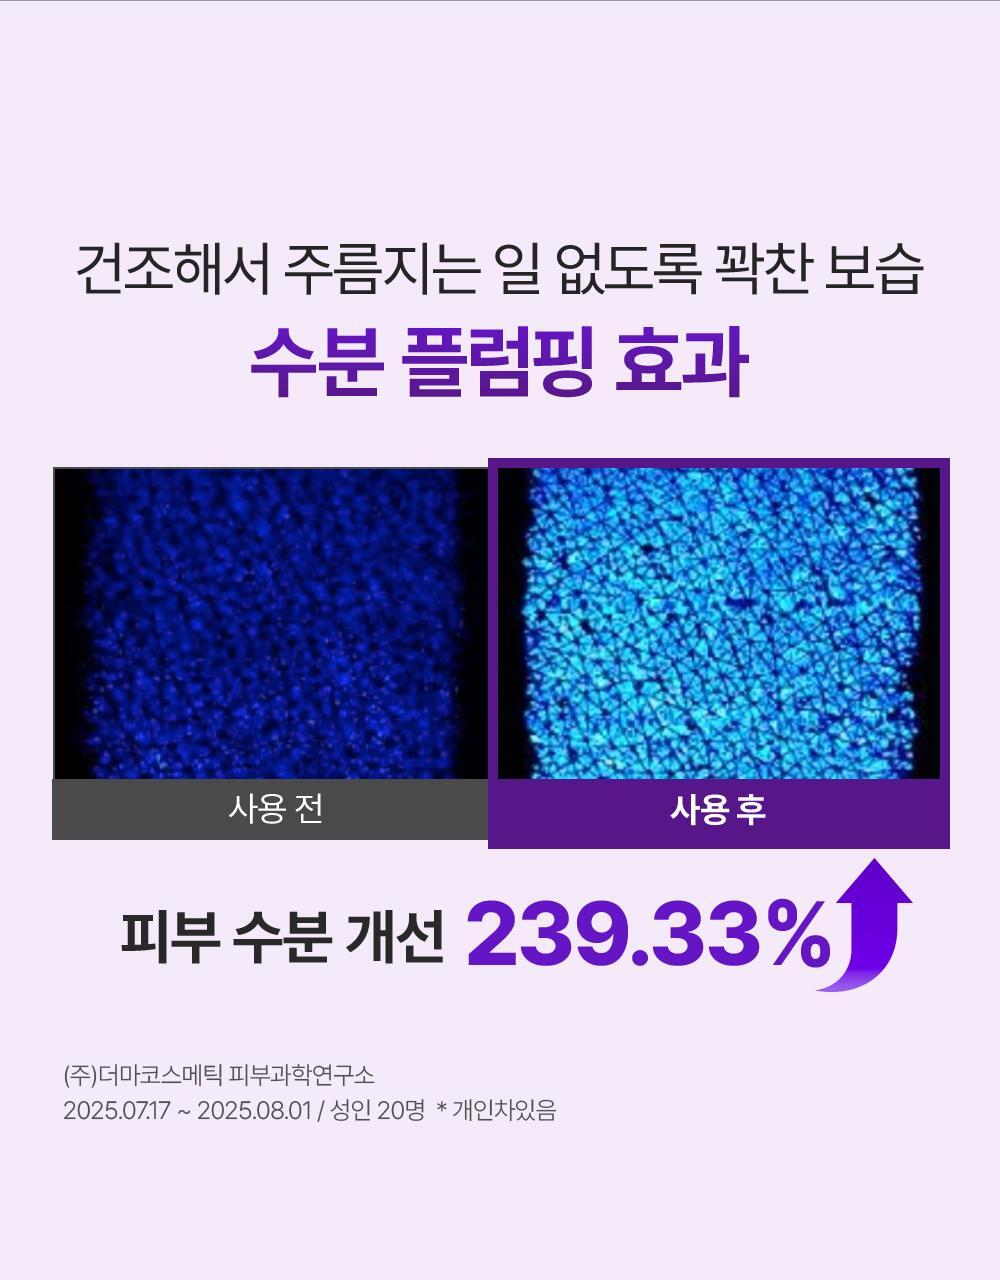

以「喚醒細胞能量」為出發點,從肌膚深層細胞層補充彈力與密度的膠原 NMN 精華。配方溫和不刺激、可作為每日安心使用的彈力保養,適合想改善肌膚鬆弛、細紋與乾燥感的人士加入日常護膚程序。

- 透明質酸 + 彈性蛋白(Elastin):補水與彈性成分,協助肌膚潤澤與彈性維持。

- Phyto Mucin + EGF:蘊含高活性高純度95%表皮生長因子EGF和植物粘蛋白,可強化肌膚深層的膠原蛋白結構。